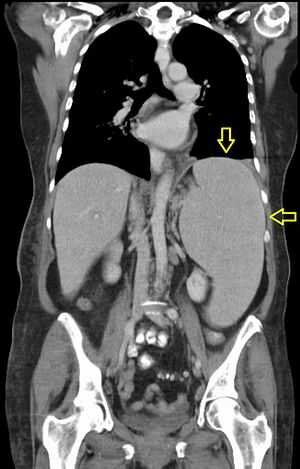

Для обследования органов брюшной полости врач применяет прощупывание (пальпацию), перкуссию. При использовании метода здоровая селезенка выявляться не должна. Для уточнения размеров селезенки используют УЗИ брюшной полости, МРТ или КТ.

Исследование, показывающее параметры селезенки, однородностью структуры. - МРТ, КТ.

Рассматривают строение органа, нервные ткани и сосудов. - Биопсия с гистологией.